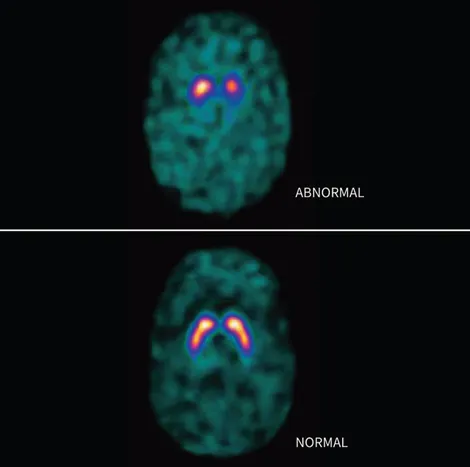

- Indic: Differentiates PD (DaT deficit) from non-DaT deficit disorders (Essential Tremor, drug-induced parkinsonism).

- Findings:

- Normal: Symmetrical, intense "comma"/"crescent" striatal uptake (caudate, putamen).

- PD: ↓ asymmetric putamen uptake, progressing to "period"/"dot" appearance.

- DaTscan (Ioflupane I-123 SPECT) differentiates Parkinson's disease (↓ striatal uptake) from essential tremor.